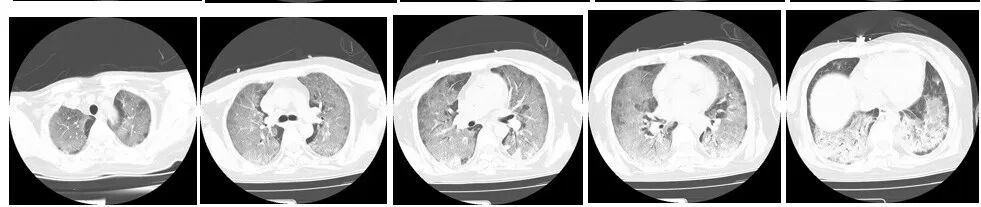

图3(2024年10月3日 D17)胸部CT双肺弥漫性渗出改变较前略吸收,伴磨玻璃影。